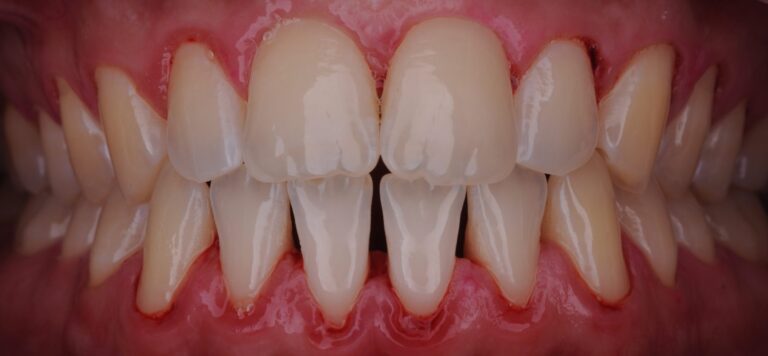

Результат:

- Сразу после процедуры:

- Камень полностью удалён

- Воспаление значительно уменьшилось

- Десна выглядит более спокойной

- Пациенту даны индивидуальные рекомендации по уходу: использование межзубных ёршиков, зубной нити, регулярность профессиональной гигиены.